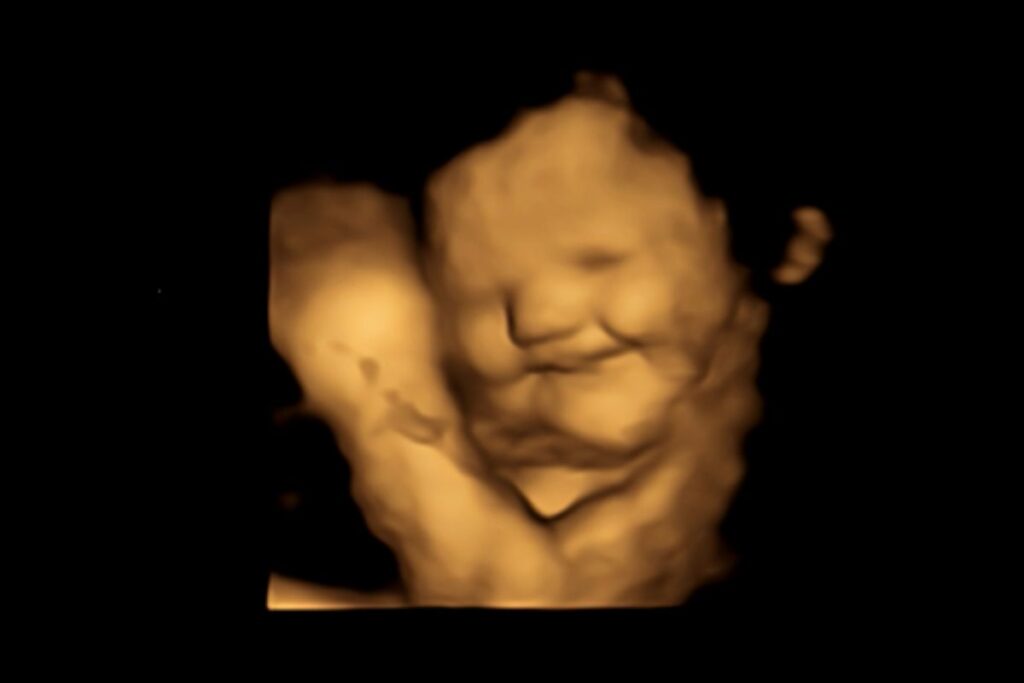

Como dito anteriormente, os cientistas perceberam que no ultrassom 4D de grávidas que ingeriram a cápsula de cenoura, o bebê sorria diante do saber. Veja esse resultado na foto a seguir: